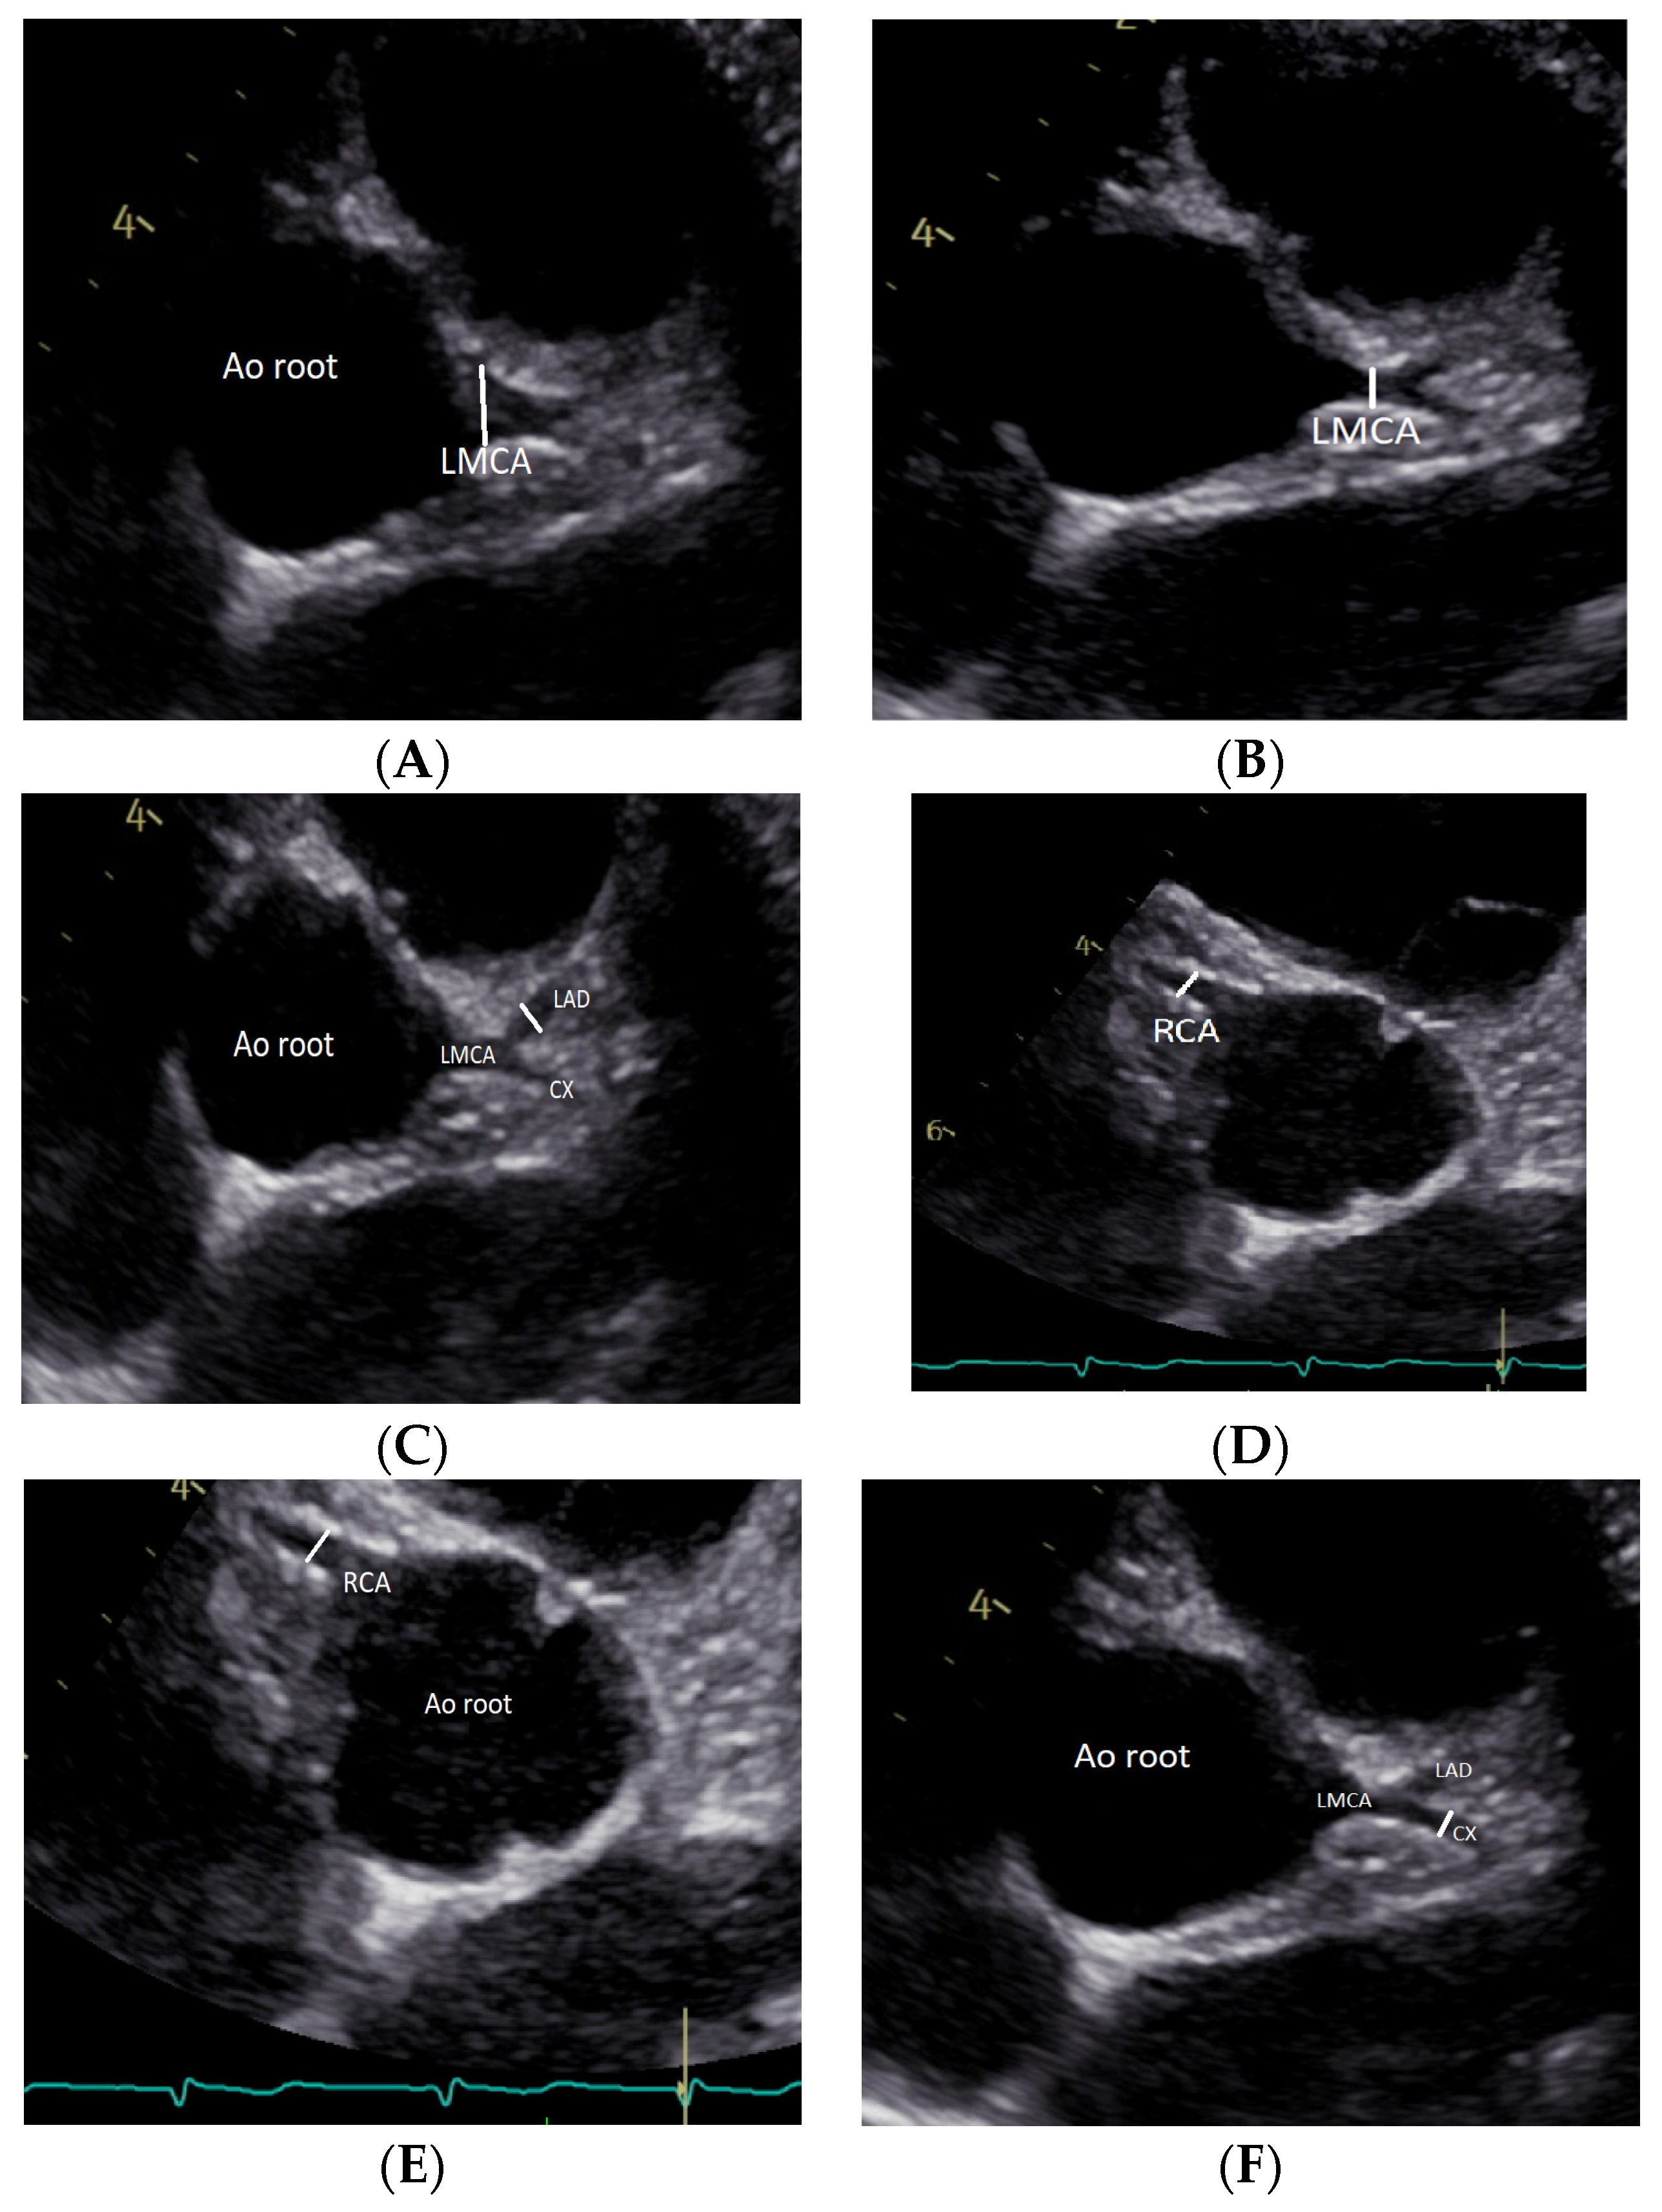

2.2. Echocardiographic Measurements